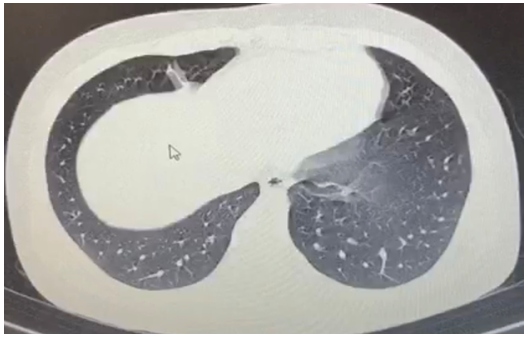

Ahead computed tomography (CT) was normal, a contrasted brain magnetic resonance was performed did not show infectious or vascular processes, a chest CT was scanned to rule out COVID-19, showing peripheral ground glass-like opacity in left dorsal lung (Figure 1). The laboratory analysis revealed a white blood cell count 7,630 per microliter lymphocyte percentage of 20 %, platelet count of 168.000 per microliter, C-reative protein of 3.5mg/L D- dimer of 100 ng/ml and INR of 1.25, cerebrospinal fluid of transparent appearance, cellularity 0.0 LDH 54, proteins 25 mg / dl, glucose 47 mg / dl, negative culture and negative viral panel, it was not possible to perform a SARS-COV-2 PCR test because of unavailability in the hospital. He had no previous contact with any positive patient for SARS-CoV 2 however, considering the hyposmia and the findings in the chest CT scan thus a real-time polymerase chain reaction assay (RT-PCR) was performed, which showed positive results for SARS-CoV-2, treatment was started on hydroxychloroquine (600 mg/day) and Lopinavir/ritonavir 400mg/100mg PO q12hr for 4 days. After the treatment started, the patient's clinical condition improved, a new test for SARS-COV2 was performed twice, being negative, so he was discharged on day 15 with an EEG that did not show epileptogenic alterations or periodic patterns but it could be perceived in the electrocardiogram lead an irregular R-R interval and a significant increase in heart rate during hyperventilation, reproducing presyncope dysautonomic symptoms (Figure 2A & 2B).

Figure 1 Radiological findings. A chest CT scan on admission showing the peripheral ground glass-like opacity in Right dorsal lung.